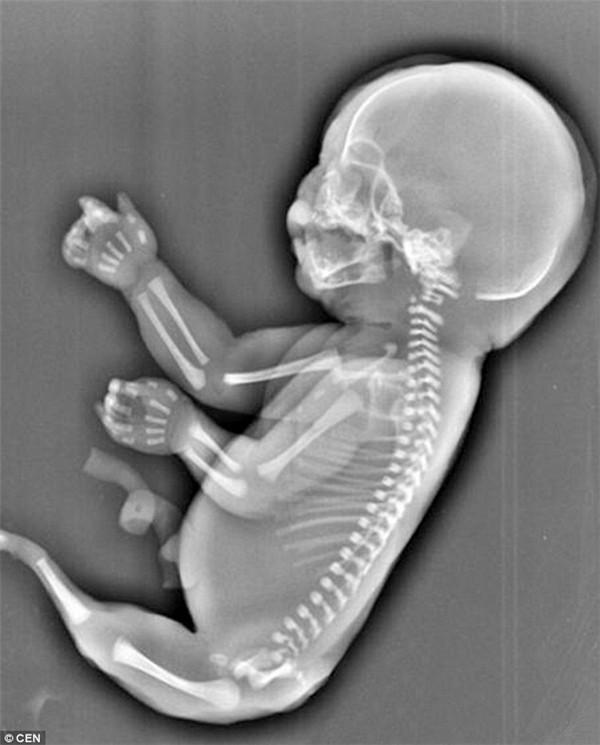

Khoa học phát triển, câu chuyện về các nàng tiên cá được khắc họa nhiều trong sách báo, tranh ảnh… dần dần được sáng tỏ. Thực chất, những đứa trẻ sinh ra có phần chân tựa như đuôi cá là bị di tật bẩm sinh hiếm gặp.

Hội chứng nàng tiên cá hay còn gọi là hội chứng người cá (hội chứng Mermaid) là một rối loạn phát triển bẩm sinh cực kỳ hiếm gặp.

Trẻ sơ sinh bị ảnh hưởng sinh ra với hai chân hợp lại một phần hoặc toàn bộ. Các dị tật khác kèm theo cũng có thể xảy ra bao gồm các bất thường ở đường sinh dục tiết niệu, các bất thường ở đường tiêu hóa, dị tật cột sống thắt lưng, xương chậu và không có hoặc kém phát triển của một hoặc cả hai thận.

Hội chứng Mermaid là một căn bệnh quái ác từ khi còn nằm trong bào thai. Ảnh minh họa

Trẻ sơ sinh bị hội chứng này có thể có một bàn chân, không có bàn chân hoặc cả hai bàn chân bị xoay ra bên ngoài. Trẻ thường không có xương cụt, xương cùng có thể có một phần hoặc không có. Các tình trạng khác có thể xảy ra với hội chứng người cá như hậu môn bị tịt, nứt đốt sống và các dị tật tim.